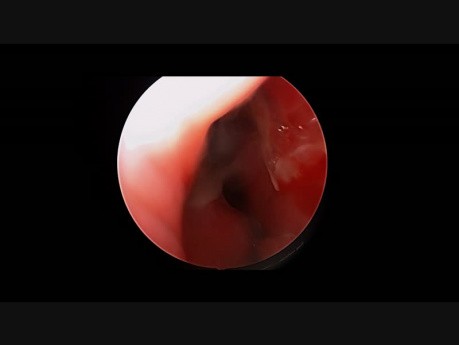

Edoskopowa septoplastyka: niewielka ostroga

Nagranie przedstawia endoskopową septoplastykę - usunięcie ostrogi przegrody nosowej po stronie lewej